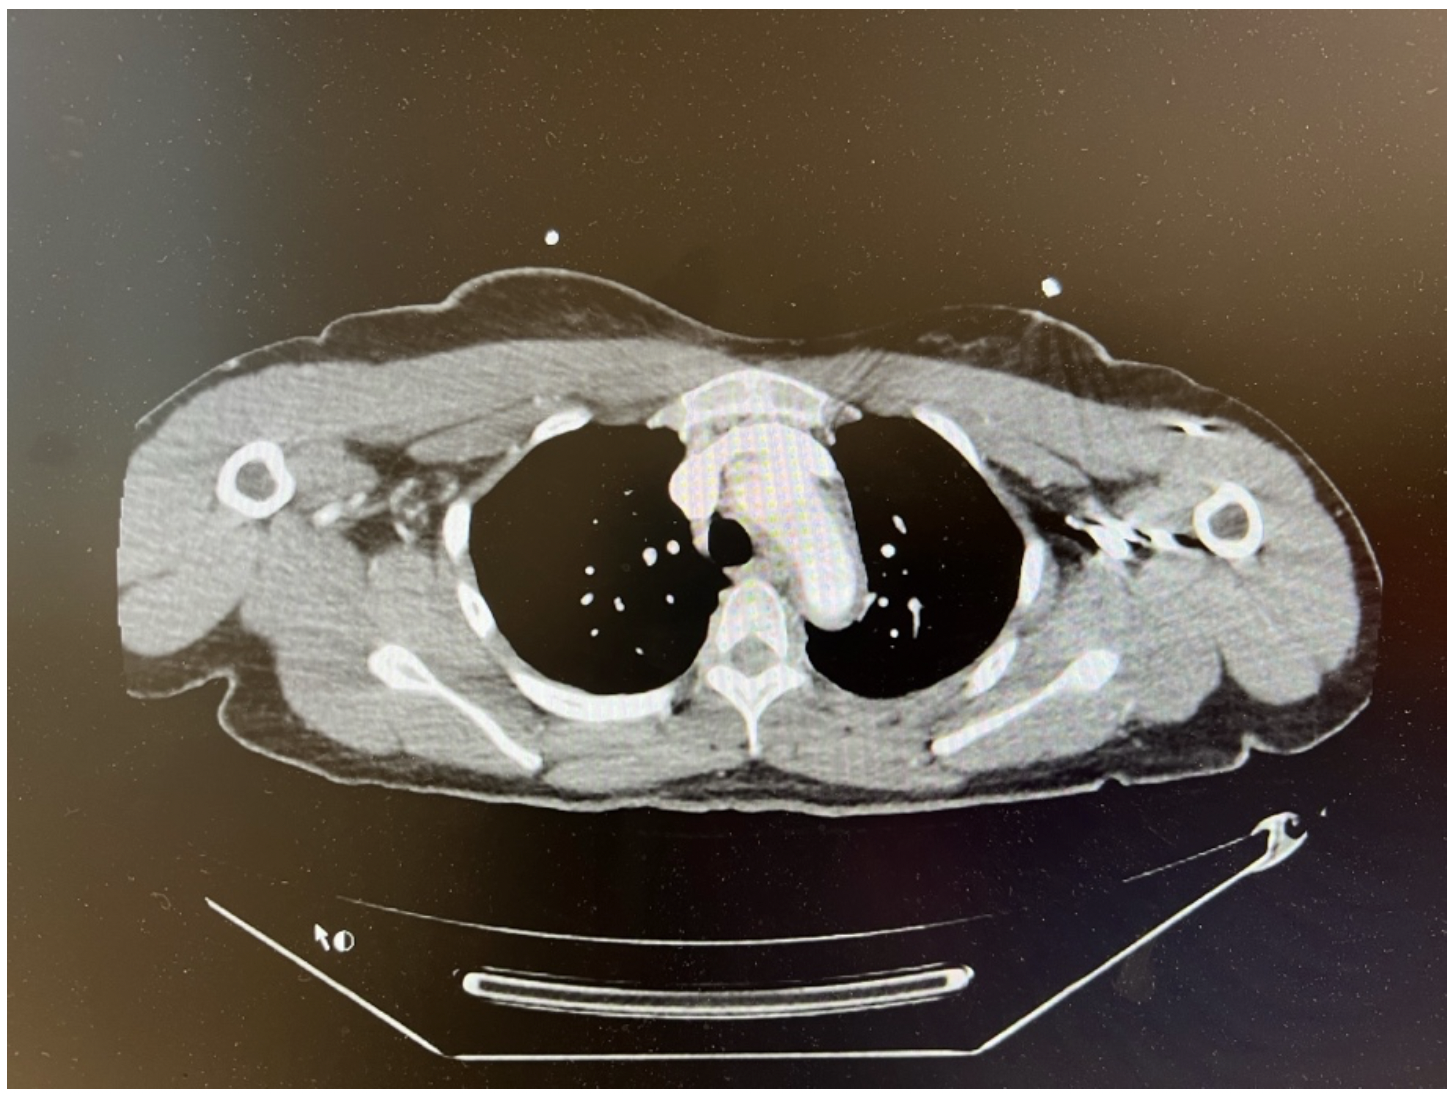

A 28-year-old right-handed woman with no significant medical history presented with aphasia and right arm weakness of 3-day duration. Noncontrast head computed tomography (CT) showed a subacute left parietal infarct without hemorrhage. The aortic wall had a 0.4-cm thickening. Figure 1 depicts the underlying inflammatory condition/edema.

As shown in Figure 2, a neck CT with contrast showed abnormal wall thickening and hyperenhancement of the aortic arch, left common carotid artery (CCA), and right carotid bifurcation. Vertebral arteries were patent and the Circle of Willis intact. The left CCA was totally occluded, as was the left internal carotid artery (ICA) through its distal cervical and proximal intracranial segments, with eventual reconstitution at the terminus and paraclinoid segments. The external carotid artery (ECA) was also occluded, so the procedure was stopped before the ECA, which would usually have been involved in cases of no occlusion. High-grade stenosis of the origin of the right ICA was noted. Of note, a Streptococcus A rapid test was positive. Inflammatory markers were marginally elevated. The patient was transferred to our tertiary medical center for further management.